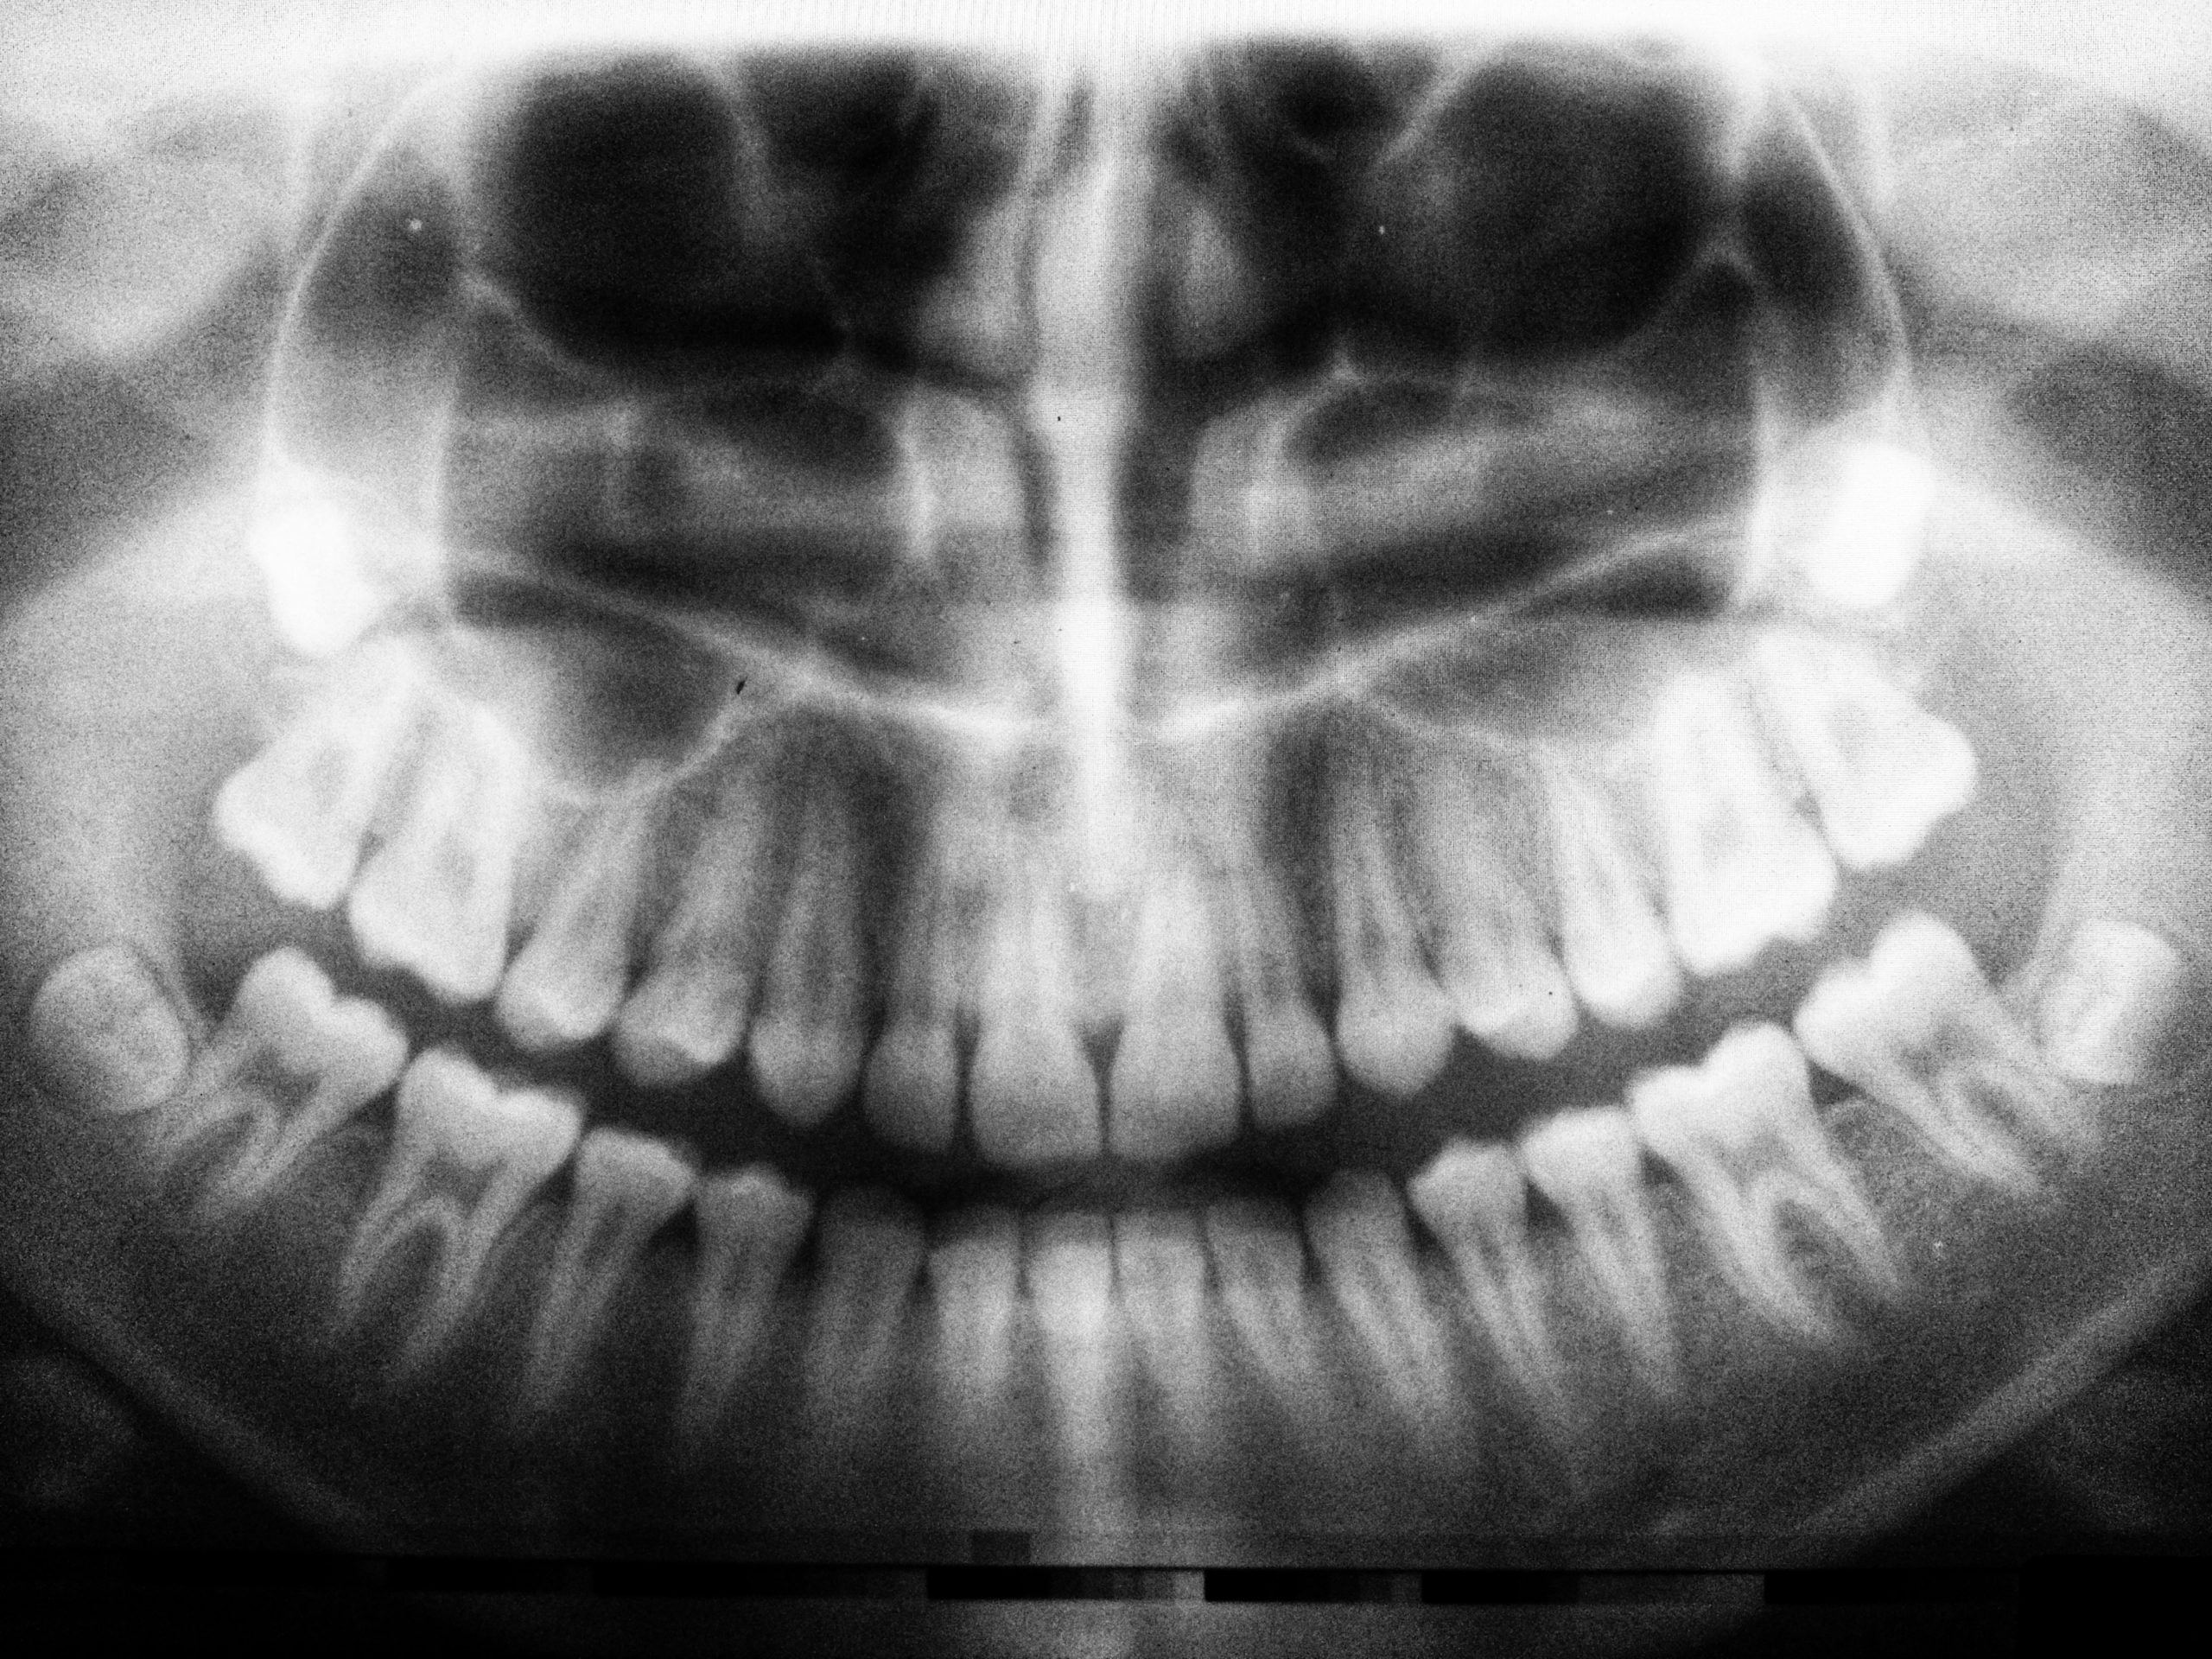

Nel nostro studio utilizziamo strumenti digitali per pianificare ogni fase del trattamento prima di intervenire. Questo significa poter studiare l’osso, la posizione ideale degli impianti, l’estetica del sorriso e la funzione nel tempo.